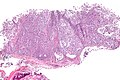

Features:[5]

• Myoepithelial cells - may be:

• Spindled.

• Plasmacytoid.

• Epithelioid.

• Clear (rare).

• Lack tubules, i.e. epithelial component.

• May be up to 10% (or 5%[6]).